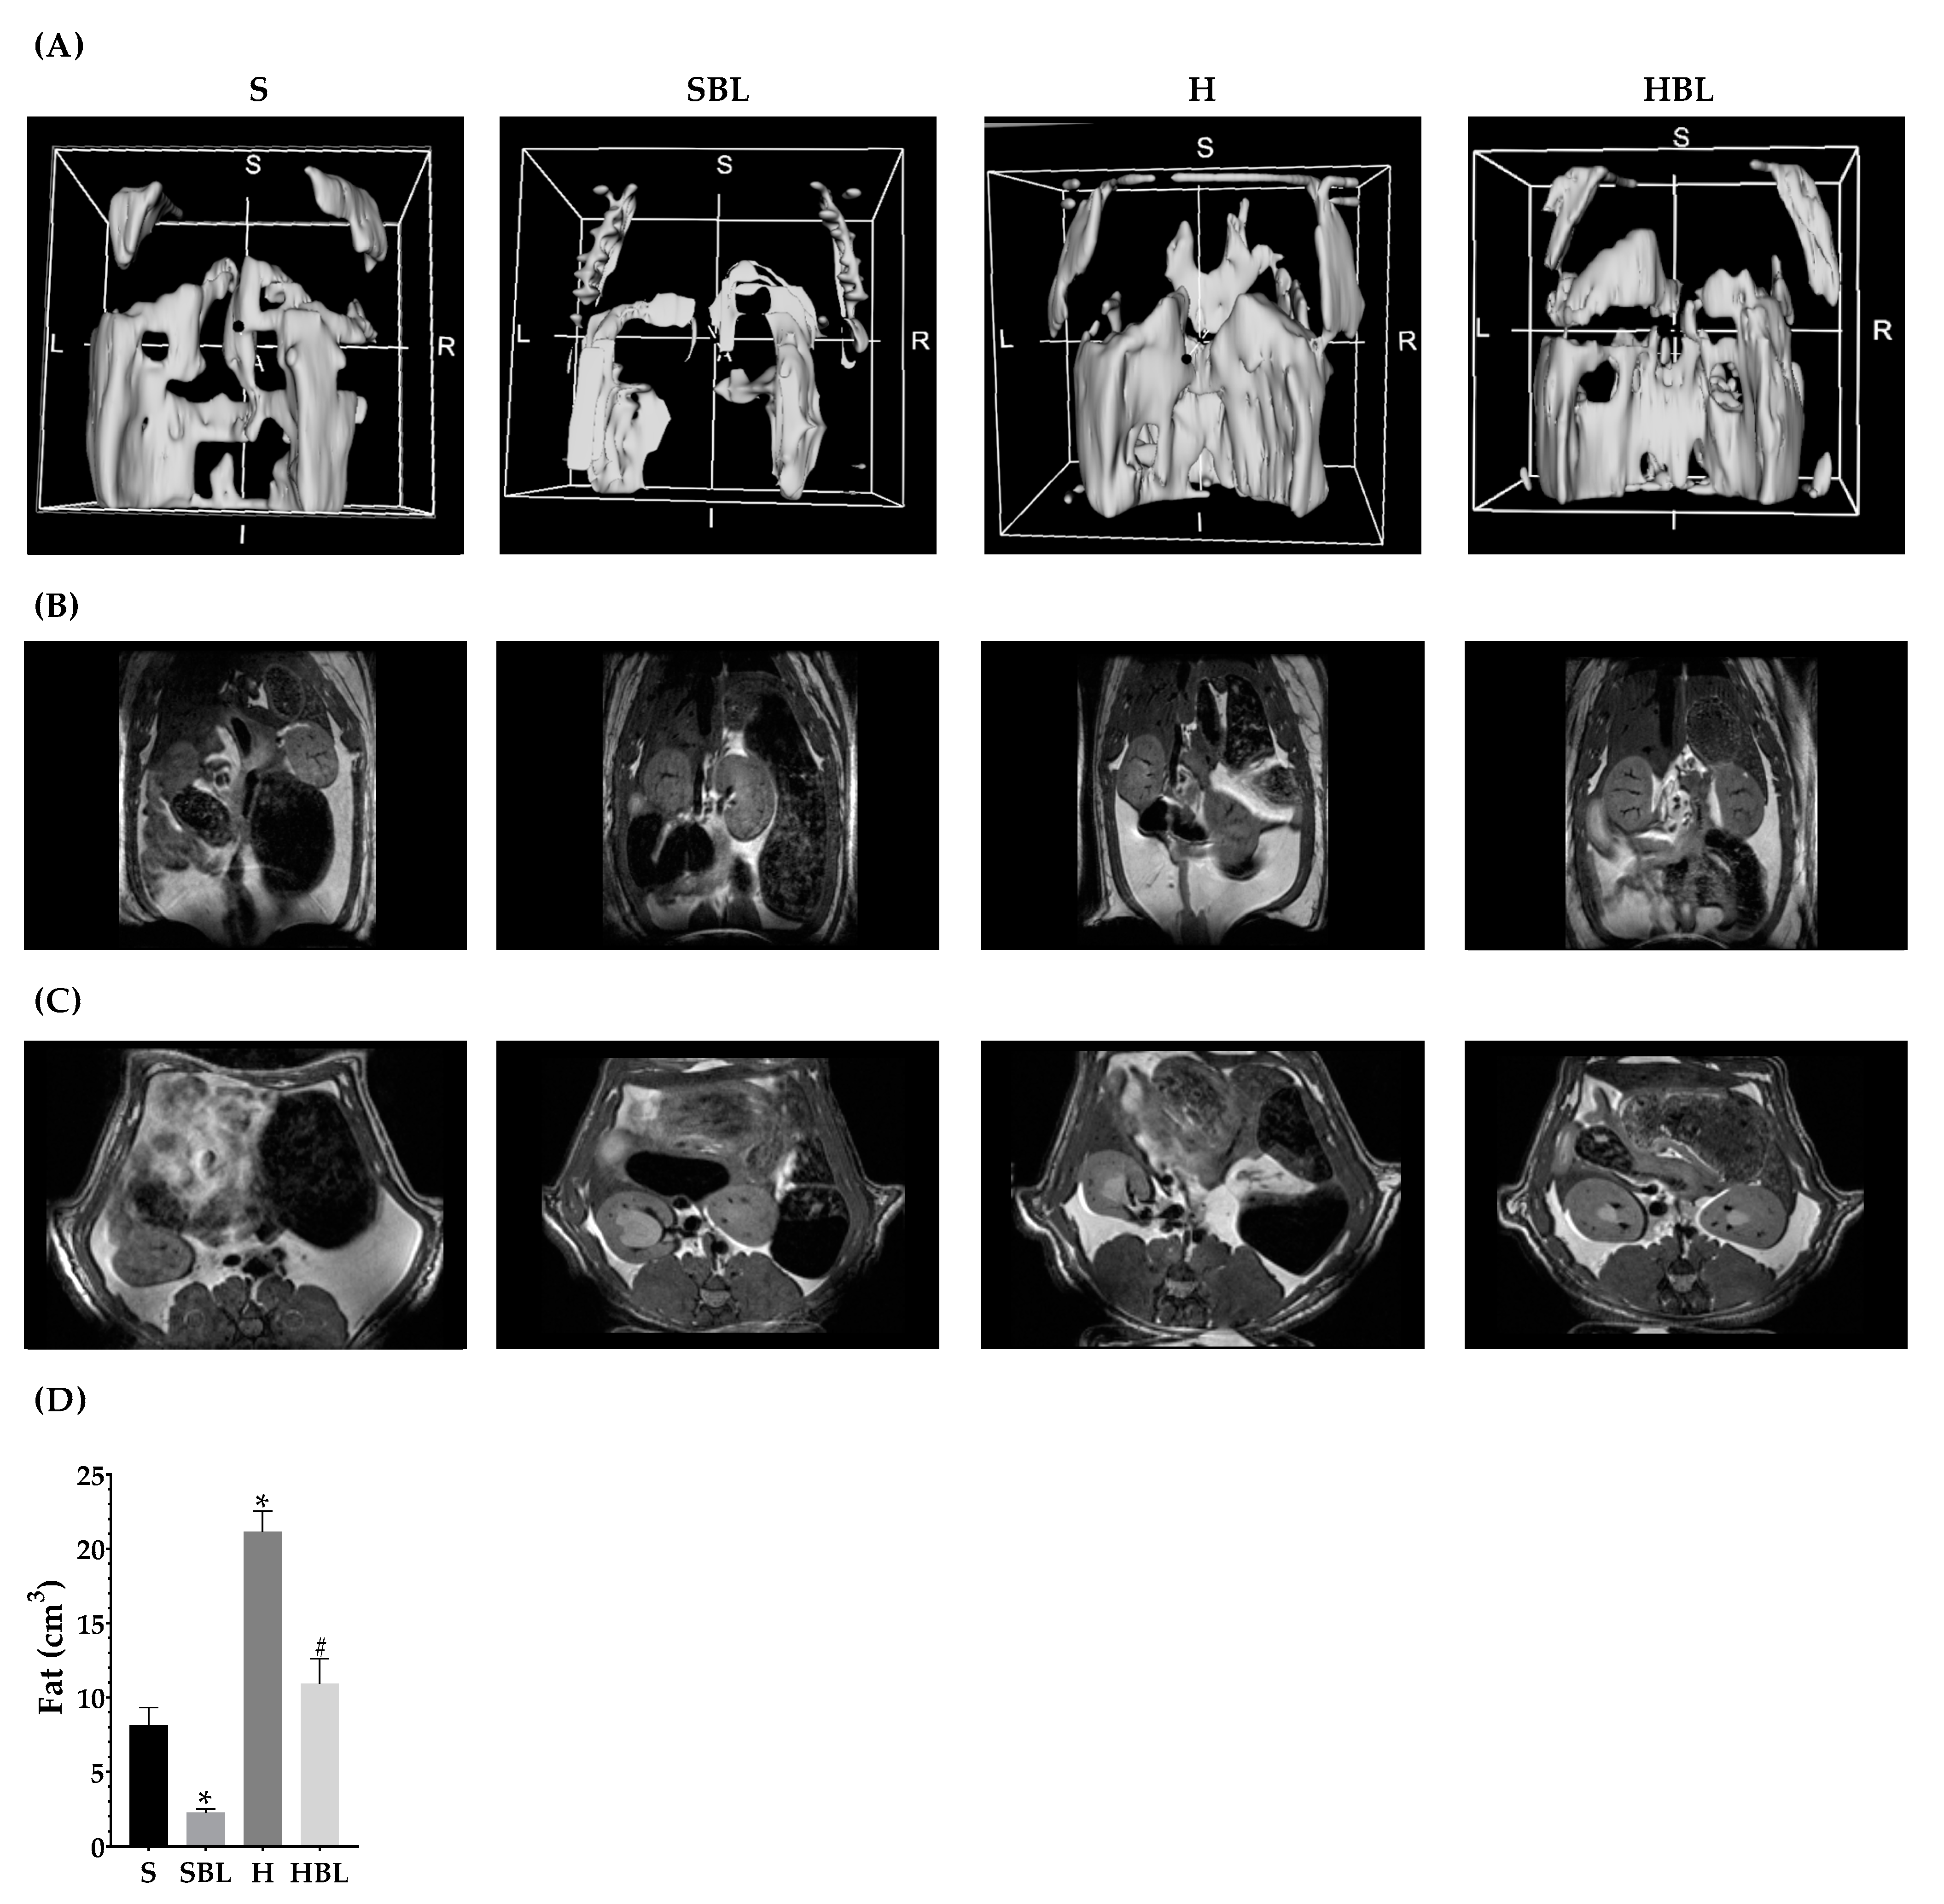

3.1. Effect of Bean Leaves on Body Fat Accumulation